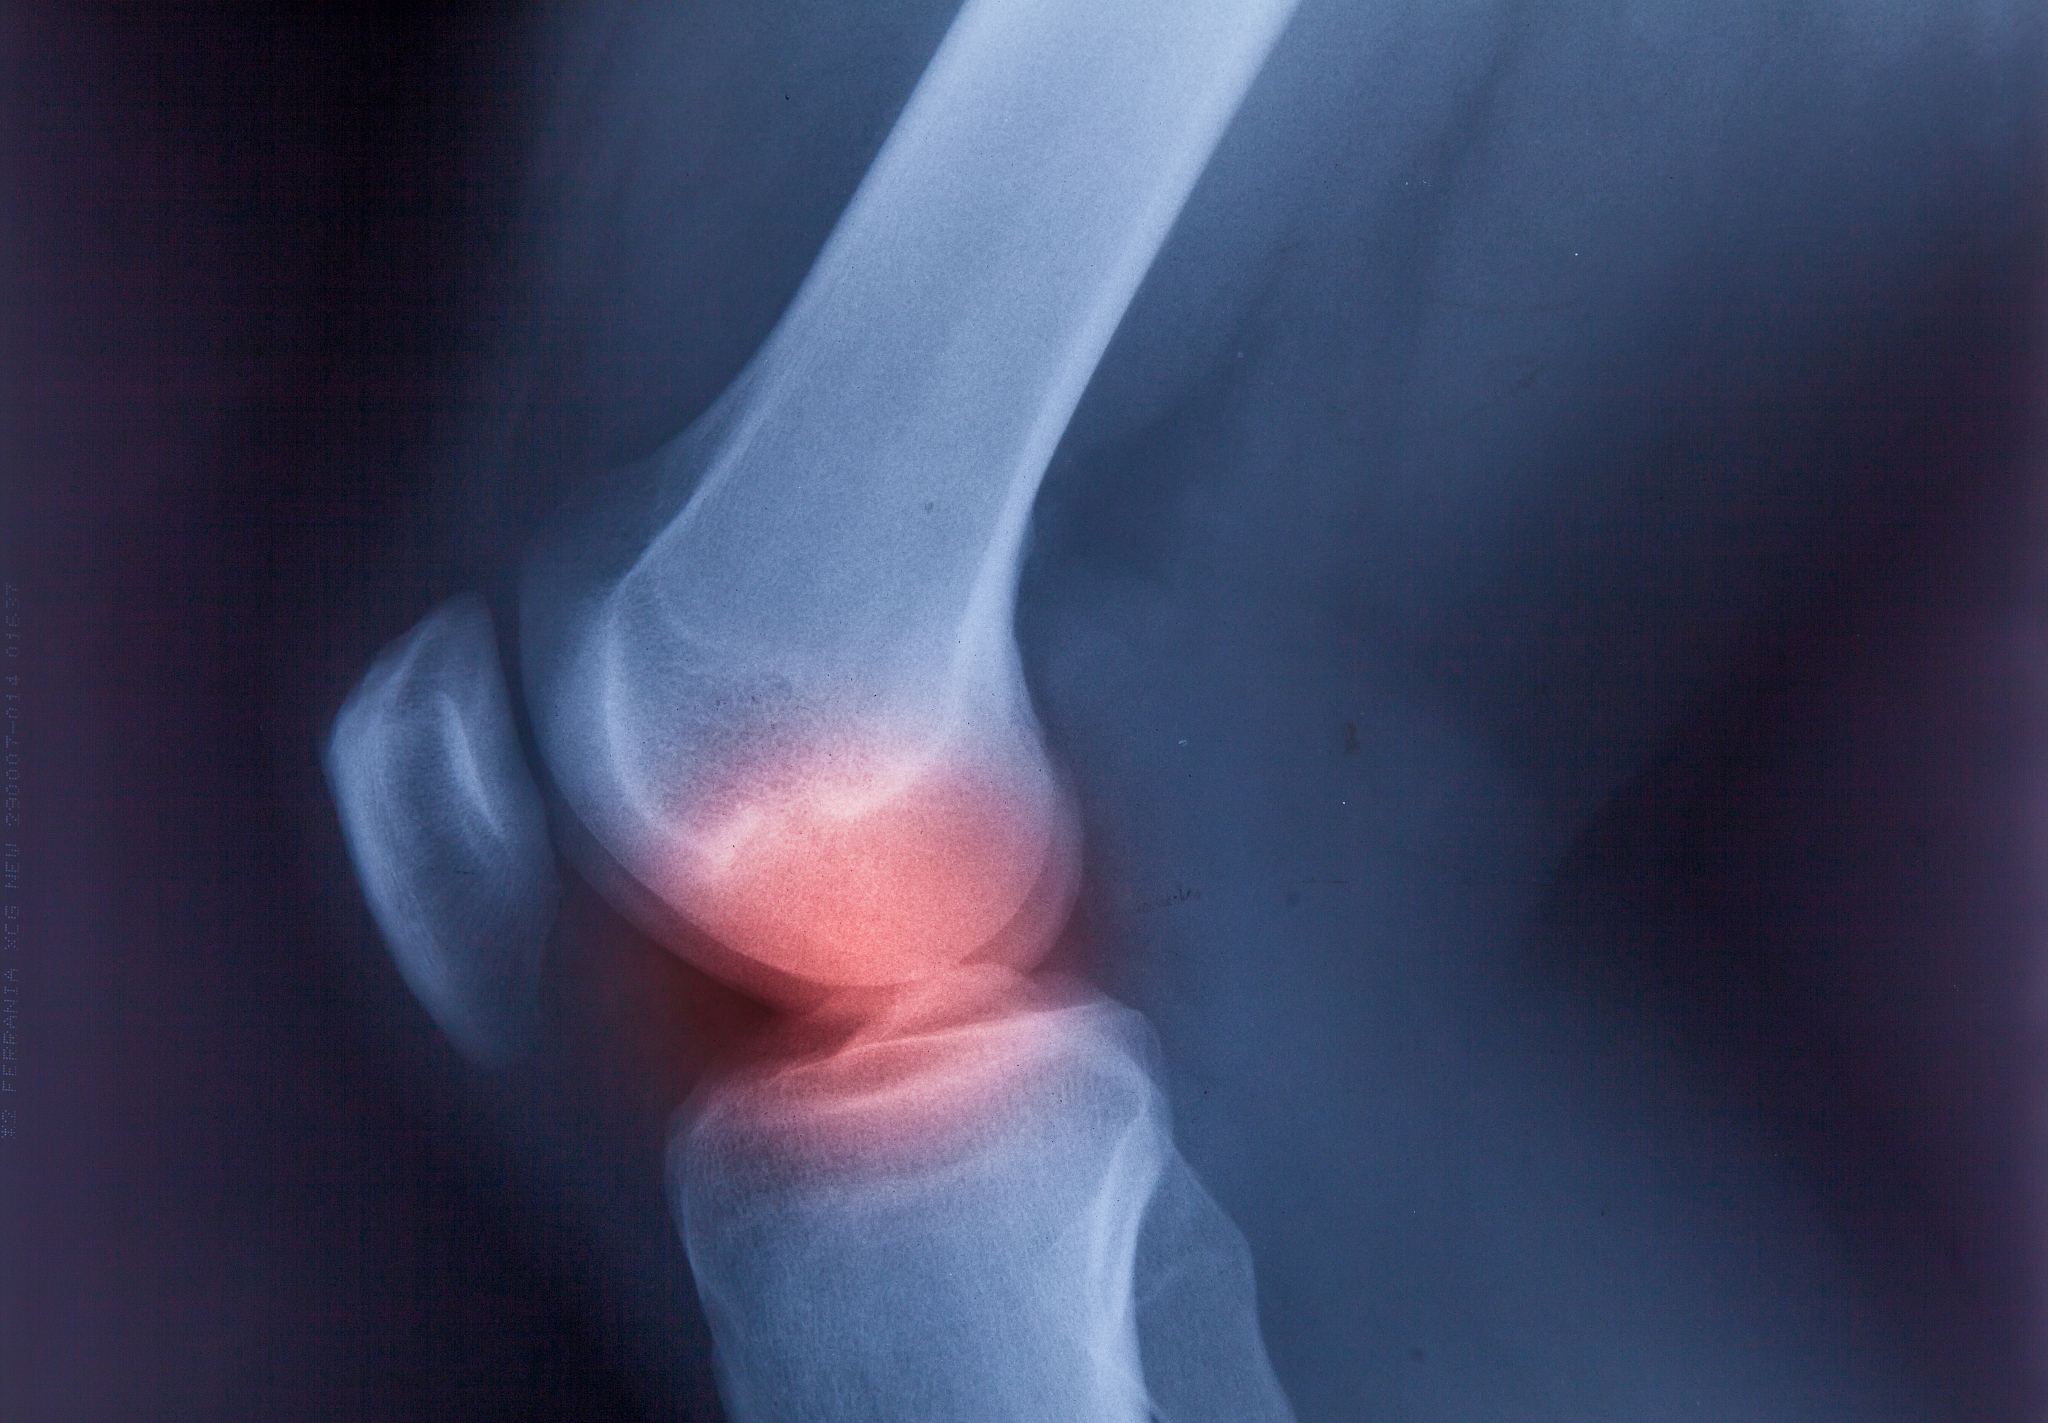

脚踝多次扭伤每次脚踝向内旋转时距骨处便会发生脆响这种情况可以恢复吗

如果脚踝多次扭伤导致距骨处发生脆响,可能表示距骨已经发生了损伤。建议您尽快就医,进行相关检查和治疗,以避免进一步损伤和加重症状。治疗可能包括物理疗法、药物治疗、手术等。同时,在康复期间也应该避免剧烈运动和重复受伤,加强脚踝的肌肉力量和稳定性,以防止再次扭伤。